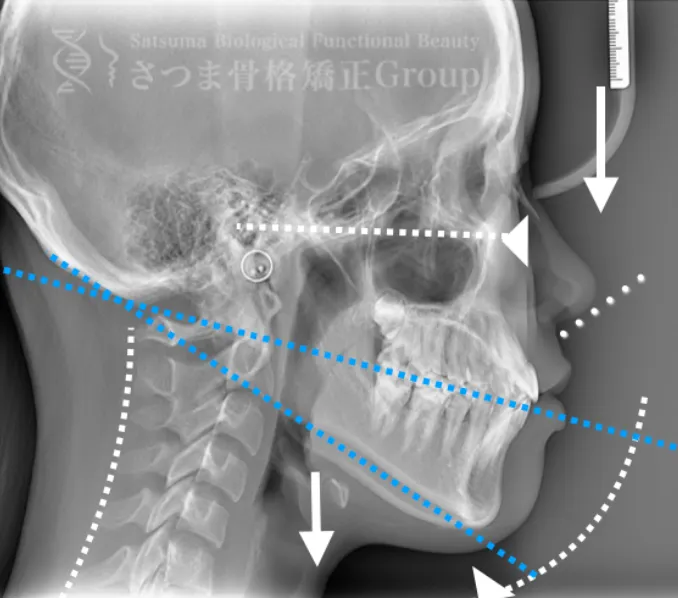

これらの問題を正確に評価するため、当院では セファロシステムによるレントゲン撮影(X-ray images) を行っています。

セファロ撮影によって 顎関節・頭蓋骨・頸椎の位置関係を客観的に可視化でき、施術前の状態を科学的に把握することが可能となります。

施術の前後で撮影したレントゲン写真を比較することで、改善の度合いや変化を一目で確認できます。